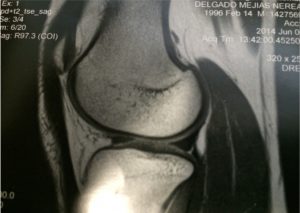

Report the outcomes of arthroscopic all-inside meniscal fixation in a large sample of soccer players with hypermobile lateral meniscus. A surgical treatment with mainly anamnestic indication.

2010-2015: 55 soccer players with hypermobile lateral meniscus treated surgically :

The diagnosis of hypermobile lateral meniscus is a clinical diagnosis only confirmed during the arthroscopy.